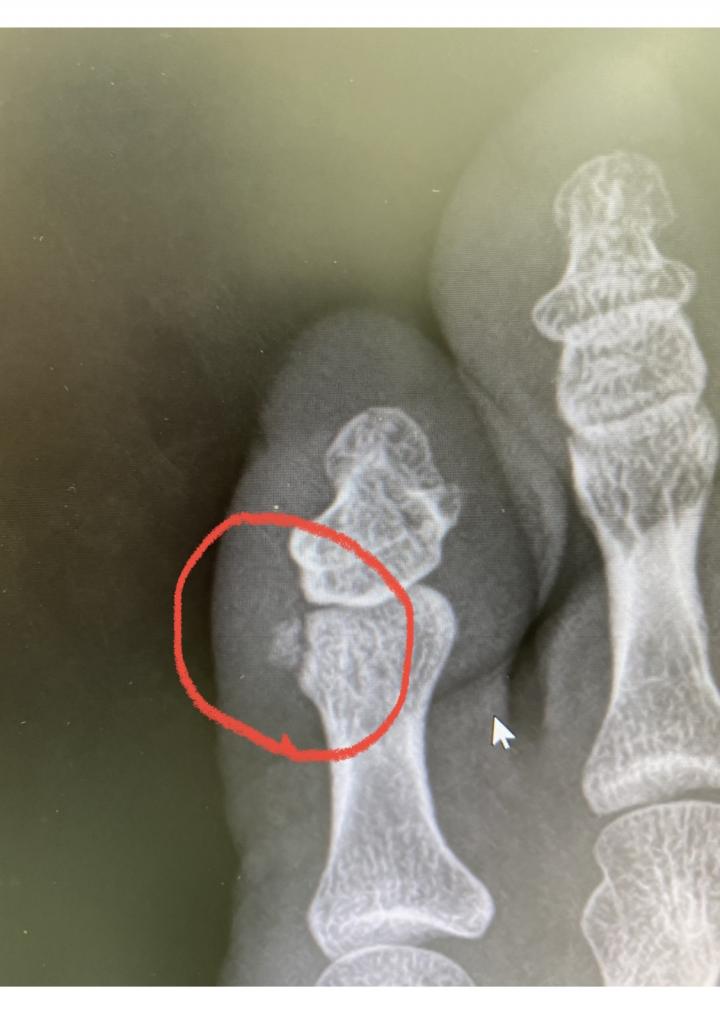

そして最後に私の足のレントゲン

ぶつけて骨が欠けました(笑)

超超超腫れるし、痛いし、靴履けないし💧

ちなみに1ヶ月弱くらいしたら、急に痛みはなくなりました♪